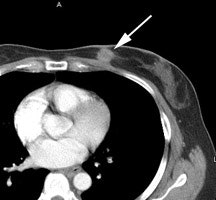

FDG PET exam for the evaluation of locoregional recurrence: The patient shown in the case below had a history of breast cancer and had developed left chest pain. She presented for the evaluation of possible metastatic disease. The CT scan revealed extensive soft tissue thickening in the left breast which was felt possibly related to scar from prior surgery and radiation therapy. There was a 2 cm lymph node in the left axilla (not shown) which was concerning for metastatic disease. Axial (center) and coronal (right) images from the patients FDG PET exam demonstrated marked increased FDG accumulation within the left breast corresponding to the soft tissue abnormality on CT. There were also multiple foci of increased uptake within the the left axilla. Biopsy revealed recurrent breast cancer. Case courtesy of CTI, The power behind PET. |

|